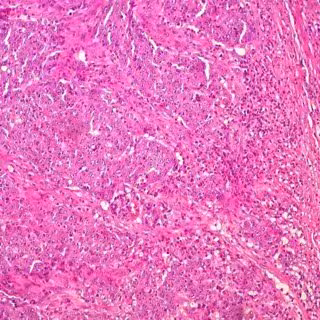

El cáncer de colon se puede curar en el 90 por ciento de los casos si se detecta precozmente, recuerda la Fundación Española del Aparato Digestivo (FEAD), con motivo del Día Mundial contra el Cáncer de Colon, que se celebra el 31 de marzo, que hace especial hincapié en participar en los programas institucionales de cribado de la comunidad donde se resida si se tienen más de 50 años o si se forma parte de los grupos de riesgo.

El cáncer de colon es el más frecuentemente diagnosticado en España, siendo el segundo en mujeres, después del cáncer de mama, y el tercero en frecuencia en hombres, después del de pulmón y próstata.

En España, se diagnostican cada año alrededor de 44.900 nuevos casos, si bien el cáncer de colon se puede curar en el 90% de los casos si se detecta precozmente.

Según los expertos los programas de cribado basados en la prueba de sangre oculta en heces y, si esta es positiva, en la colonoscopia, son la medida más efectiva para reducir la incidencia y la mortalidad del cáncer de colon tanto por coste, como por eficacia y por la calidad de vida que proporciona a los pacientes.

Según los datos disponibles, una vez realizado el test, se estima obtener sangre oculta en heces positiva entre 5%-8% de las pruebas realizadas, y es solo a este grupo a quienes se les indica un paso más de control con la colonoscopia. De estas colonoscopias, entre un 40 y un 50% presentan pólipos o lesiones precancerosas, que según sus características pueden tratarse durante dicho procedimiento.